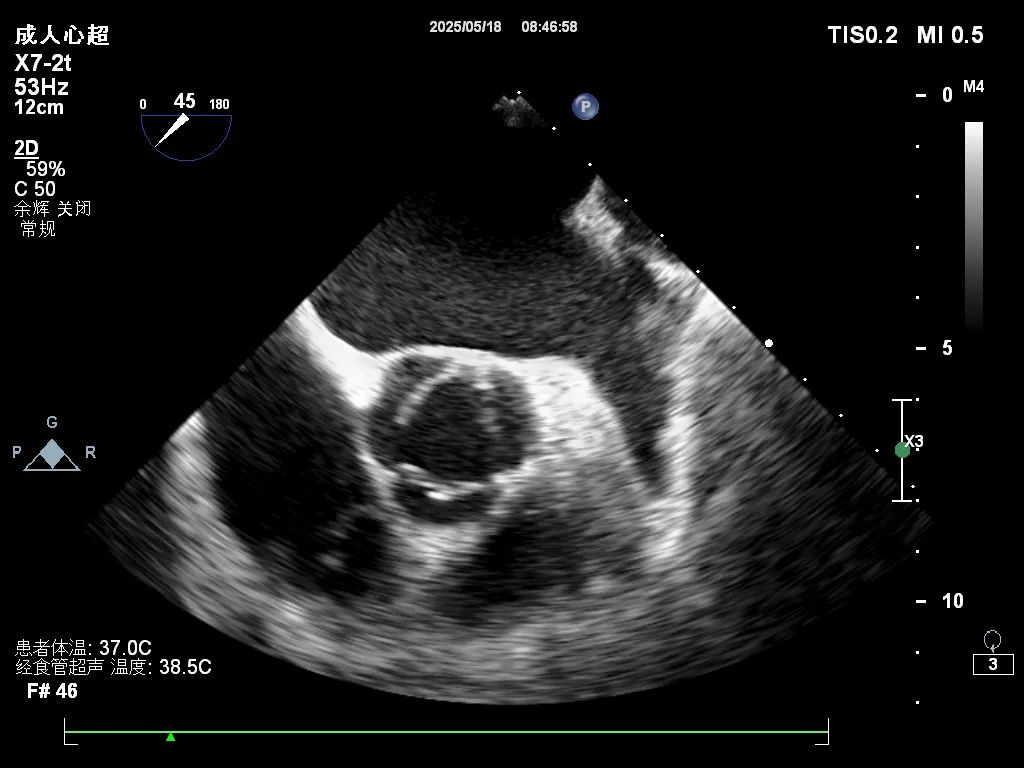

近日,我院功能检查科成功开展经食道超声心动图(TEE)检查新技术,进一步提升了我院心血管疾病的诊断水平。

经食道超声克服了传统经胸超声的局限性,通过食道从后方近距离探查心脏,显著提高了心房、房间隔及心脏瓣膜的图像分辨率,尤其适用于各类心脏瓣膜病、先天性心脏病、心耳内血栓及感染性心内膜炎等疾病的精细诊断,为手术方案的制定和术后评估提供了重要依据。

此项技术由王鹏医生率先开展,他曾赴北京安贞医院专项进修经食道心血管超声技术,积累了丰富的操作与诊断经验。目前,该技术已顺利应用于多名房颤及可疑卵圆孔未闭患者,检查过程安全、结果精准,受到临床医生和患者的一致好评。